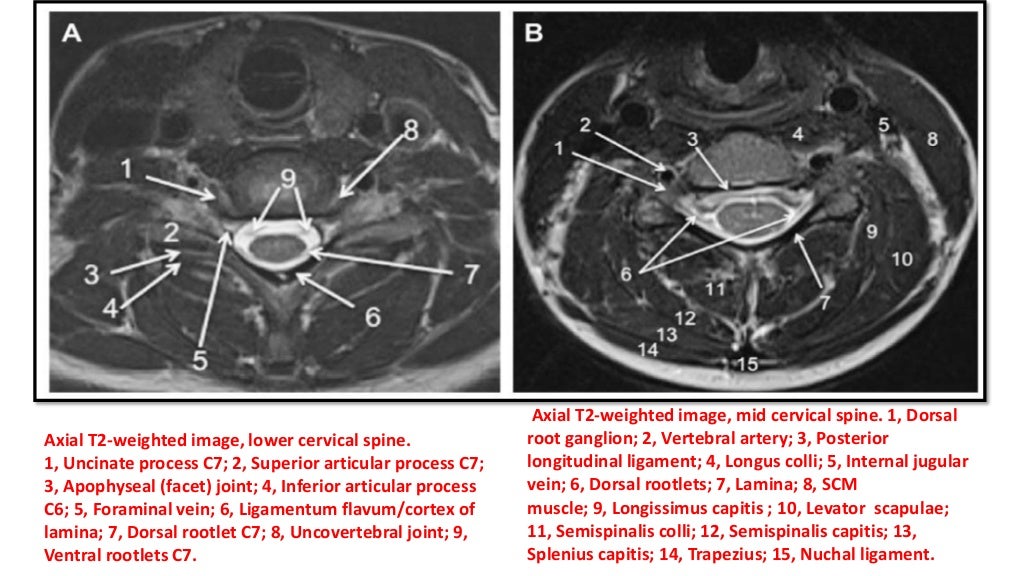

Anatomy Mri Cervical Spine . this case illustrates the normal anatomy features found in the cervical spine mri. understanding cervical spine mri. magnetic resonance imaging (mri) is instrumental in evaluation of symptomatic cervical spine degeneration and guidance of surgical treatment. Cervical spine mri is a painless and safe imaging method that uses a strong. your cervical spine is made up of 33 bones. this mri cervical spine (c spine) cross sectional anatomy tool is absolutely free to use. Although c1 (atlas) and c2 (axis) have unique characteristics and c7 (also termed. Please refer on normal spine imaging examples article for more. Use the mouse scroll wheel to move. Anatomically, your spinal cord can be grouped into five sections: